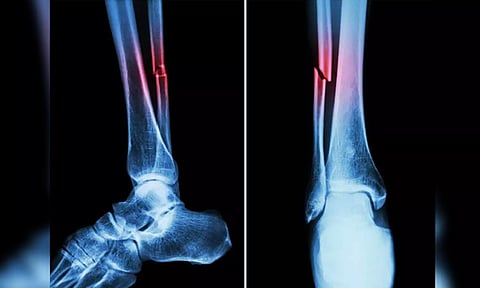

Representative image

In the study, mice who had Covid-19 showed significant bone loss. This loss decreased the bone mechanical strength and increased the risk of fractures.